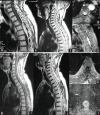

Purpose: The spinal epidural angiolipomas are rare expansive processes made of mature lipomatous and angiomatous elements. They often have a benign character. Their etiology, pathogenesis remains uncertain, and it is a cause of spinal cord compression. The magnetic resonance imaging is the most important neuroradiological examination. Histological examination is the only examination to confirm the diagnosis. Surgery is the treatment of choice.

Methods: A retrospective study of all patients operated on for a spinal epidural angiolipoma at the Department of Neurosurgery at the National Institute of Neurology of Tunis between January 2000 and December 2014 (15 years) was performed. The aim of this study is to describe the clinical, radiological, histological characteristics and the treatment of this tumor.

Results: A total of nine patients were operated from January 01, 2000 to November 30, 2014. The average age of our patients was 51 years with ages that ranged from 29 to 65 with a male predominance. The period between onset of symptoms and diagnosis ranged from 24 months with an average 12 months. Posterior localization of the tumor was seen in all patients. Surgical resection was performed for all cases. The postoperative course has been satisfactory, with a complete recovery of neurological functions in all patients.